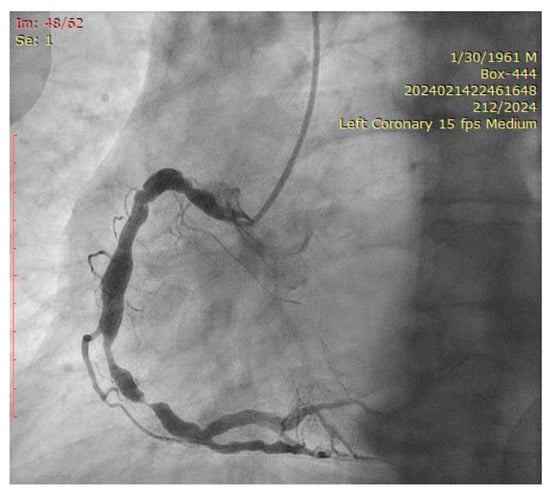

2. Case Presentation